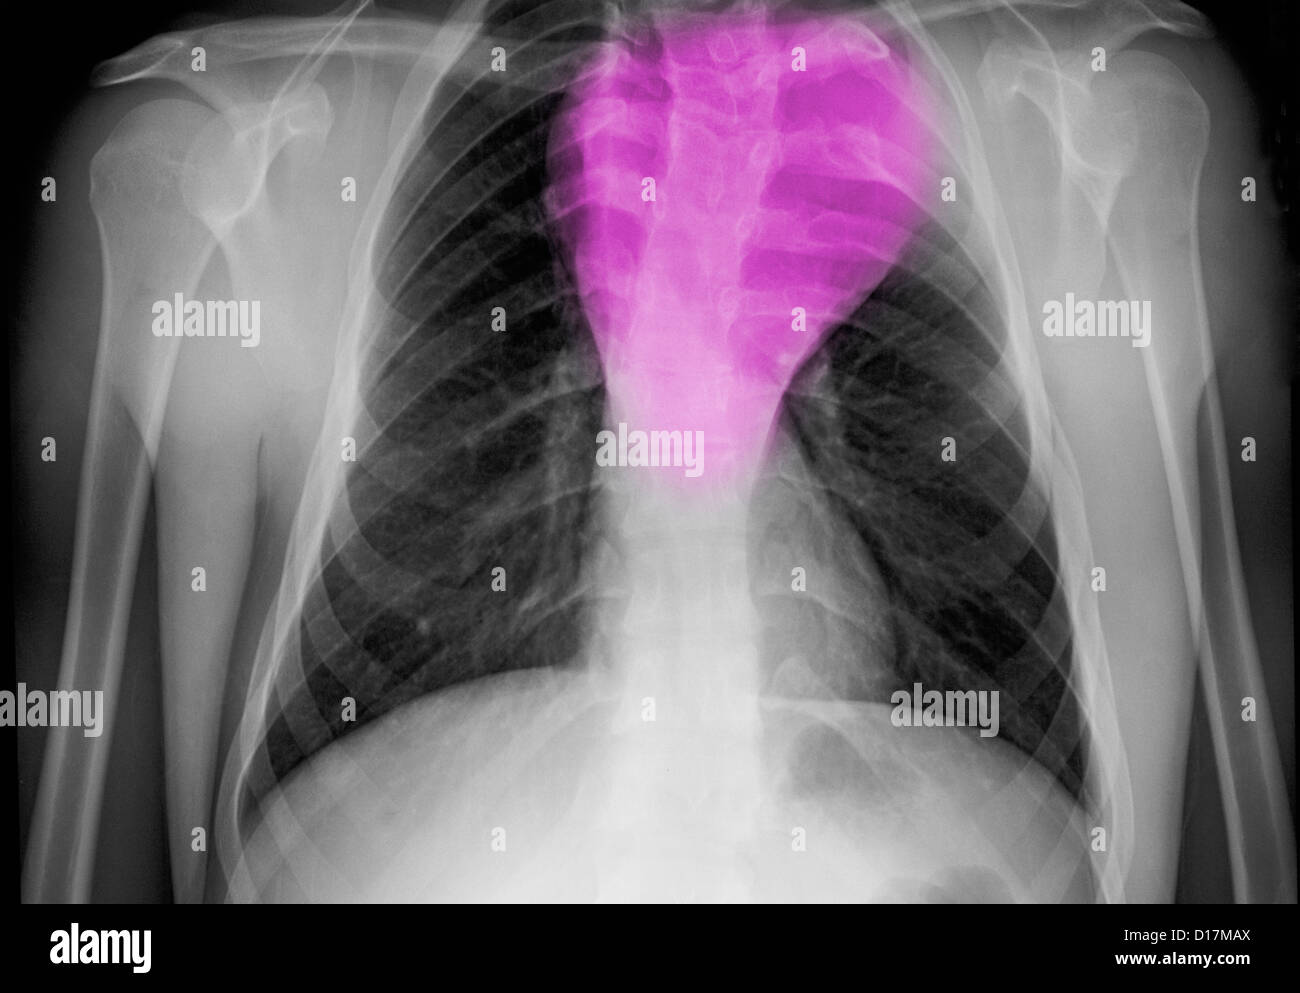

X Ray Durch Menschliche Brust Brusthohle Zeigt Gutartiger Tumor Schatten Auf Die Lunge Hamartoma Und Atemwege Stockfotografie Alamy

Anschließend tastet er die Brust sorgfältig ab und ordnet gegebenenfalls bildgebende Verfahren an, denn Gewebeveränderungen in der Brust lassen sich in der Regel gut mit Ultraschall (Sonographie) oder einer Mammographie darstellen Um einen bösartigen Tumor auszuschließen, entnimmt der Arzt meist eine Gewebeprobe. Gutartige Lungentumoren entstehen durch spontane Neubildung von körpereigenem Gewebe, gelegentlich ausgelöst durch Entzündungsprozesse Die neu entstandenen Zellen haben häufig ihre spezifische Funktion des ursprünglichen Gewebes, aus dem sie stammen, verloren und sind nun nichts weiter als raumfordernd. Benign brain tumour, ct scan gutartiger tumor stockfotos und bilder pituitary tumour, ct scan gutartiger tumor stockfotos und bilder US President Donald Trump walks across the South Lawn upon return to the White House in Washington DC on Mary 15 18 Trump returned from Walter Reed.